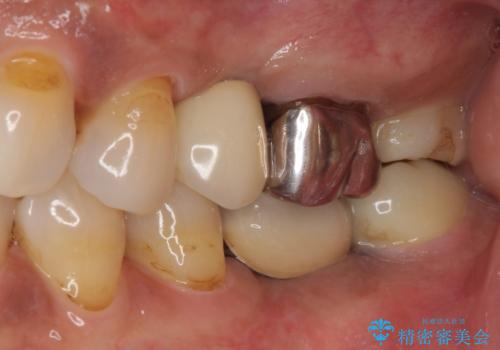

- 銀歯の装着されている奥歯がしみるとのことで来院された患者様です。

銀歯周辺の歯が欠けており、むし歯も進行している状態であったので、オールセラミッククラウンにて補綴治療を行うこととしました。

仮歯に変えた時点でしみる症状はなくなり、オールセラミッククラウンはまるで自分自身の歯のような舌触りとなり、大変満足していただきました。